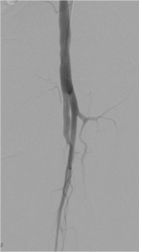

医院检查双下肢动脉CTA示:腹主动脉下段、双侧髂总动脉、双侧髂内动脉及右侧髂外动脉多发粥样硬化;左侧髂外动脉、双侧股浅动脉及左胫前动脉闭塞。